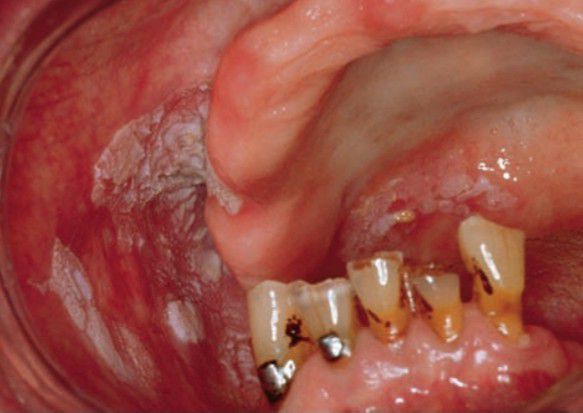

Proliferative verrucous leukoplakia

Females more often affected than males Recurrent/persistent; multiple sites typical Progression from simple keratosis to well-differentiated verruciform lesions High risk of malignant transformation to verrucous carcinoma or squamous cell carcinoma.